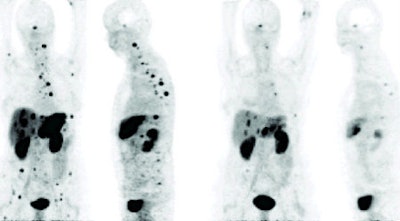

In this study, Bi-213 DOTATOC was synthesized using a microwave-assisted labeling protocol. A total of 21 patients who previously had shown resistance to treatment with the radioactive isotope yttrium-90 or lutetium-177 DOTATOC were treated with escalating doses of Bi-213 DOTATOC therapy. Doses ranged from 1 to 10 GBq up to 21 GBq.

The researchers then assessed response with gallium-68 DOTATOC PET/CT, contrast-enhanced sonography, MRI, digital subtraction angiography, and tumor markers. In addition, markers were monitored for hematologic, kidney, and endocrine toxicity during and after treatment.

| Response to Bi-123 DOTANOC treatment observed in patients with tumors resistant to previous therapy with yttrium-90 and lutetium-177. Image above shows shrinkage of liver lesions and bone metastases after therapy with 11 GBq of Bi-123 DOTANOC. Image below shows response of multiple liver lesions after therapy with 14 GBq of Bi-123 DOTANOC. Images courtesy of SNM. |

Morgenstern and colleagues found that the labeling protocol for Bi-213 DOTATOC provided reliable doses of the treatment at a clinical level. In addition, patients tolerated the increasing doses well, and there was no acute kidney, endocrine, or hematologic toxicity.

Most importantly, the researchers observed shrinkage of the primary tumors, as well as liver and bone metastases.